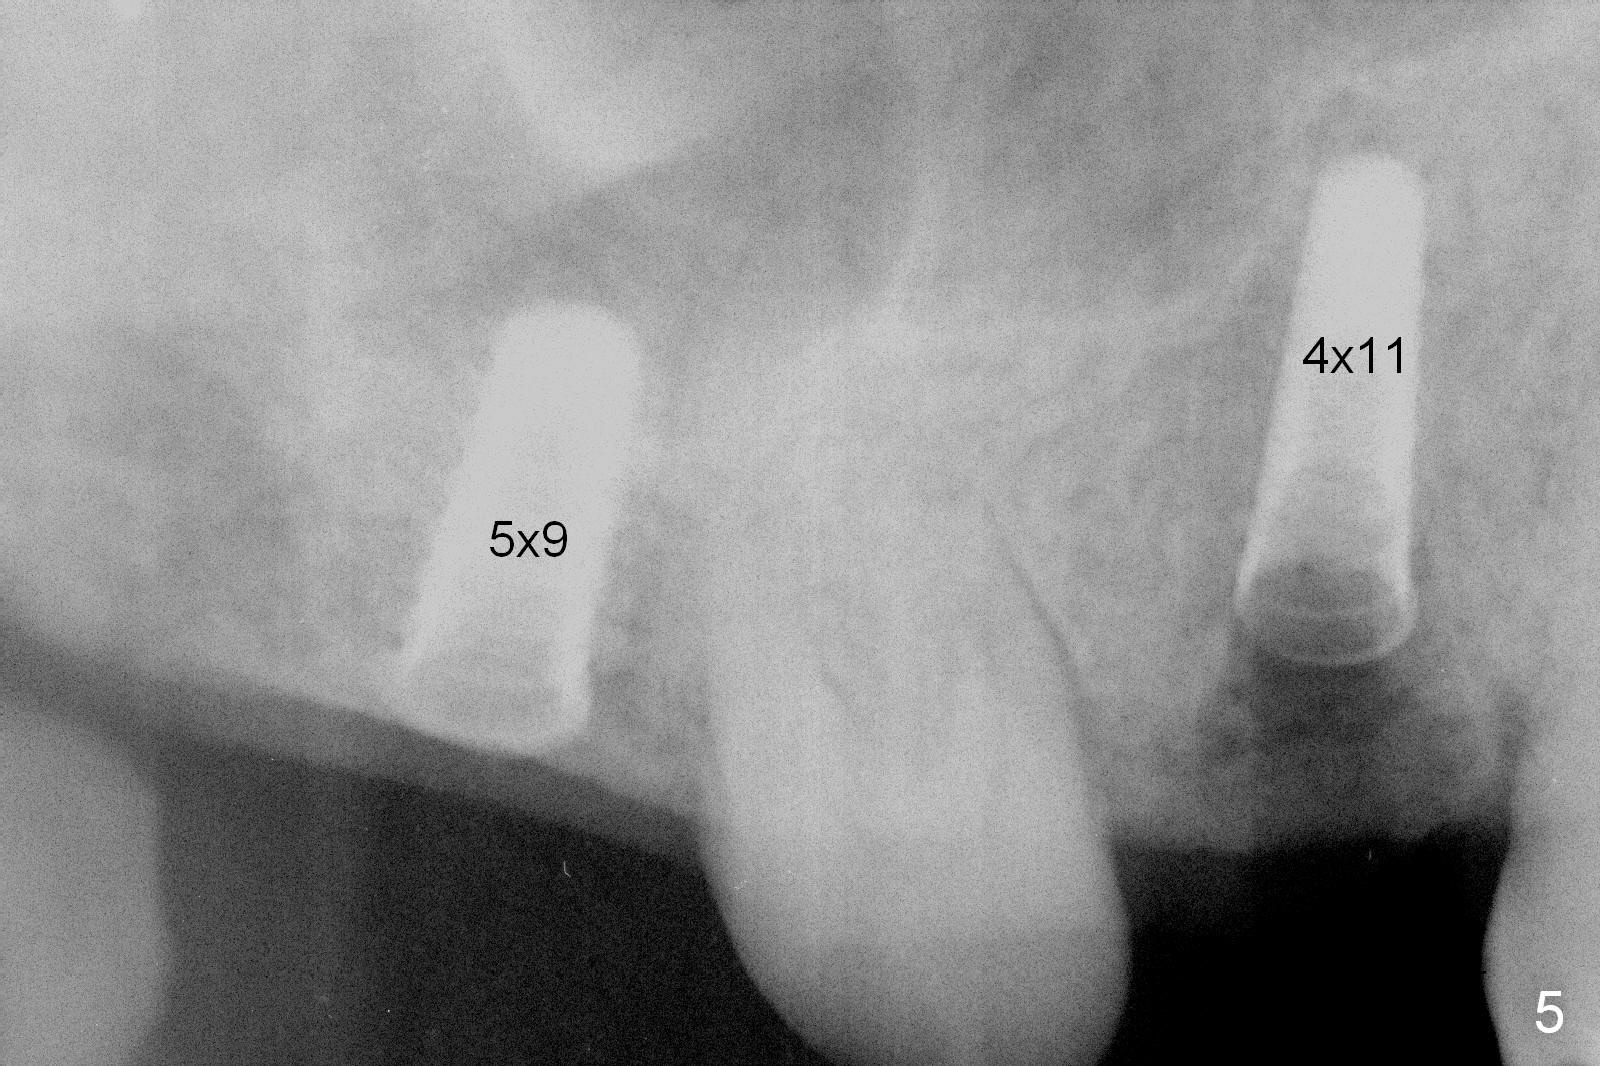

Preop exam shows posterior occlusal collapse (Fig.1) with #3 lost crown and #4 residual root. There is no ridge atrophy at #2 buccopalatally (Fig.2). The root stump of the tooth #4 is oblong, apparently consisting of 2 roots (Fig.3). There is a pointed septum at #4 socket (Fig.4, severe palatal wear of the anterior teeth (^)). After the septum is flattened with surgical handpiece and #8 round bur, 1.6 mm drill is used to start osteotomy in the septum, followed by Magic Drills (MD) and Magic Expanders (ME) alternatively. Osteotomy at #2 is initiated with Magic split, followed by MD and ME in the same manner. Dummy implants are tried in (Fig.5). Because of limited vertical height, Magicore (5.5x9(1) mm) is placed at #2, while a 4x13 mm FC implant 1-2 mm deeper than usual at #4 (Fig.6, ~ 55 Ncm). When a 5x4(2) mm pair abutment is placed at #4, there is no clearance between the Magicore at #2 and the abutment and the opposing dentition. A splinted provisional is fabricated at #3 and 4 to increase the posterior vertical height (Fig.7 P,8). In fact the occlusal contact is confined to the portion of the provisional at #3. The provisional has to extend to #4 to keep bone graft (Fig.6 *) and collagen plug in place. Liquid food is recommended at least 2-3 weeks, since there is no functional occlusal contact on the left. When the wound heals at #4 approximately 2-3 weeks, the splinted provisional can be sectioned with removal the portion at #4 to reduce micro-movement. By the evening the patient is doing well without nasal hemorrhage (sinus lift at #2 (Fig.6 *) or TMJ disturbance (due to increased vertical height).